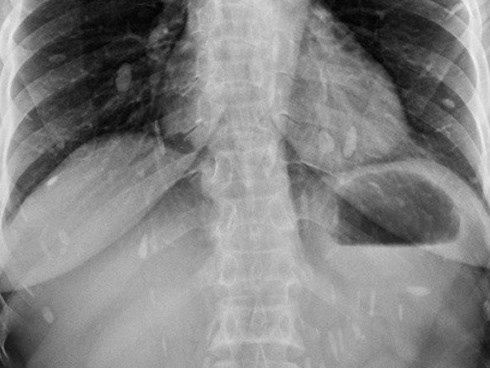

Sán bò lúc nhúc trong phổi nam thanh niên khiến ai cũng kinh hãi: Chuyên gia cảnh báo loại đồ ăn gây chứng bệnh này

Sán lá phổi hoành hành trong phổi của nam thanh niên, khi được tra hỏi mới vỡ lẽ là do thói quen ăn sống món ăn quen thuộc này.